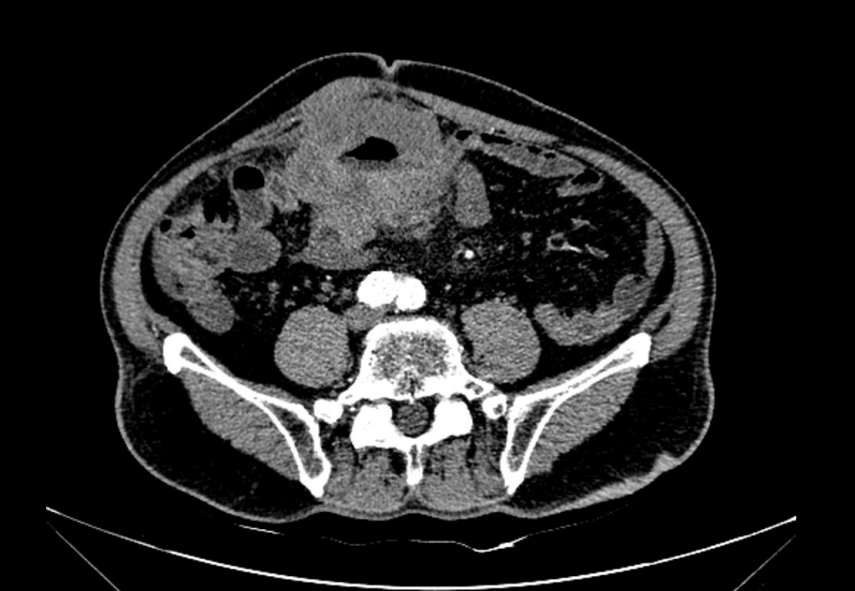

76岁的彭伯因自觉腹部包块一月余,前往广州市花都区人民医院胃肠外科就诊。腹部增强CT检查发现约8cm×6cm的巨大实性占位性病变,肿瘤已明确侵犯小肠系膜及邻近腹壁组织,并伴有区域淋巴结转移。更为棘手的是,彭伯同时合并冠心病、高血压、糖尿病等十余种基础疾病,身体机能储备差,手术耐受性面临挑战,风险极高。